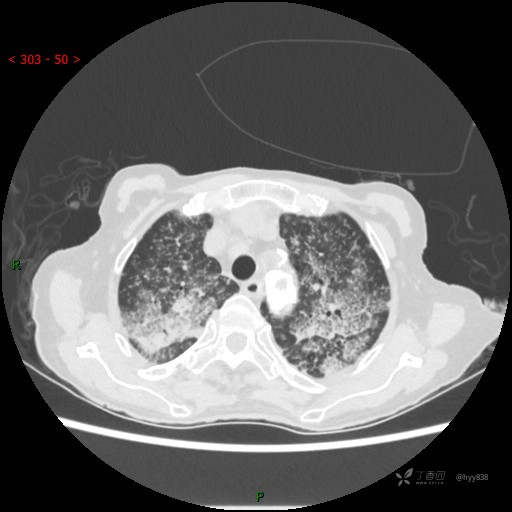

肺部弥漫性、疑难病变,感染或肿瘤?一元论或二元论?贴贴精彩---结果公布~

患者性别:女

患者年龄:73岁

主诉:反复发热10余天

简要病史:患者10余天劳累后出现发热,最高体温达39.5℃,无畏寒、寒战、鼻塞、流涕,无头晕、头痛,无心慌、胸闷、胸痛,无咳嗽、咳痰、气喘,无反酸、烧心、恶心呕吐,无腹痛、腹胀等不适,于2022-5-31至当地中医医院住院治疗,诊断为重症肺炎,予以抗感染、抗病毒等对症支持治疗,仍反复发热,现为求进一步诊治,至我院门诊就诊,门诊以“重症肺炎”收入我科。 起病以来,患者精神、饮食、睡眠差,大小便正常,体力下降,体重无明显变化。

体格检查:T 38℃ P 102次/分 R 17次/分 BP 142/85mmHg,SPO2 84%(未吸氧)。神志清楚,呼吸稍急促,查体合作,咽部充血,未见明显脓点,颈软,全身皮肤黏膜及巩膜未见黄染,浅表淋巴结未触及肿大。双肺呼吸音粗,未闻及明显干湿啰音,HR 102次/分,律齐,各瓣膜区未闻及病理性杂音。腹部平坦,腹软,无压痛,肝脾肋下未触及肿大。双下肢轻度水肿。生理反射存在,病理征阴性。

临床诊断:重症肺炎

胸部CT平扫